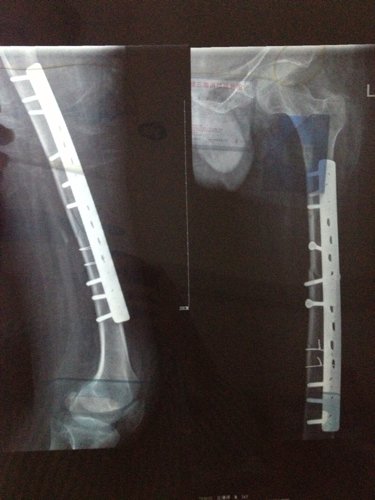

你好医生!左腿原来有小儿麻痹证,就在上个月11号不小心跌倒骨折13号做手术加钢板!现在在家休养。现在腰很痛?是怎么回事,有过性生活。现在简单吃两种药?请问医生像我这种情况会不会很难恢复原来那样?是不是还要吃些什么?还有要不要外敷些什么?还要腰很痛怎么办,谢谢!

病情分析: 图上所见,复位固定都还不错。 指导意见: 骨折的治疗重点是有效牢靠的固定。药物是次要的可以不服。也要注意尽量不要做对愈合不利的活动。除非是肌肉的锻炼等。